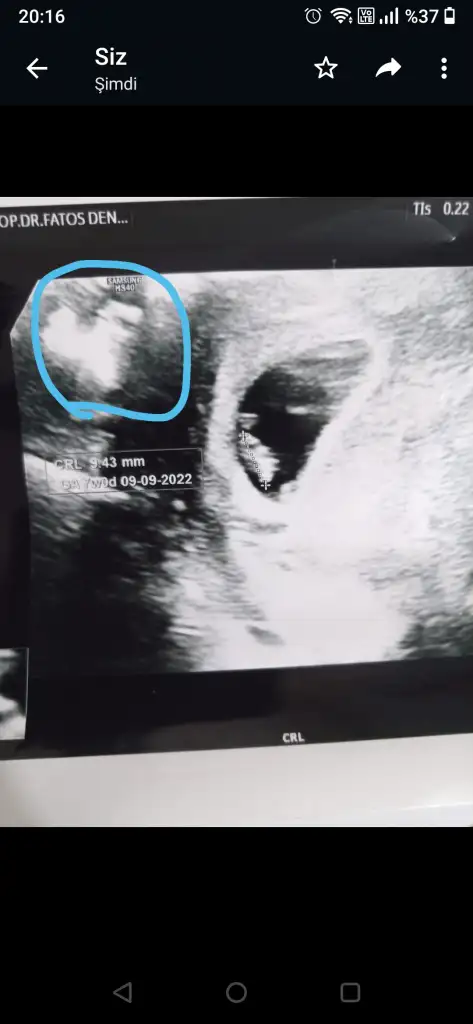

Goruyorum canim da anlamadim . Doktor bisey soyledimi ?Kizlar ultrasonumda isaretledigim şeyi siz de görüyor musunuz

Doktorunun numarasını almadın mı canım? En iyisi ona sormak ben de merak ettim ama bi sıkıntı yoktur inşaallah yaKizlar ultrasonumda isaretledigim şeyi siz de görüyor musunuz